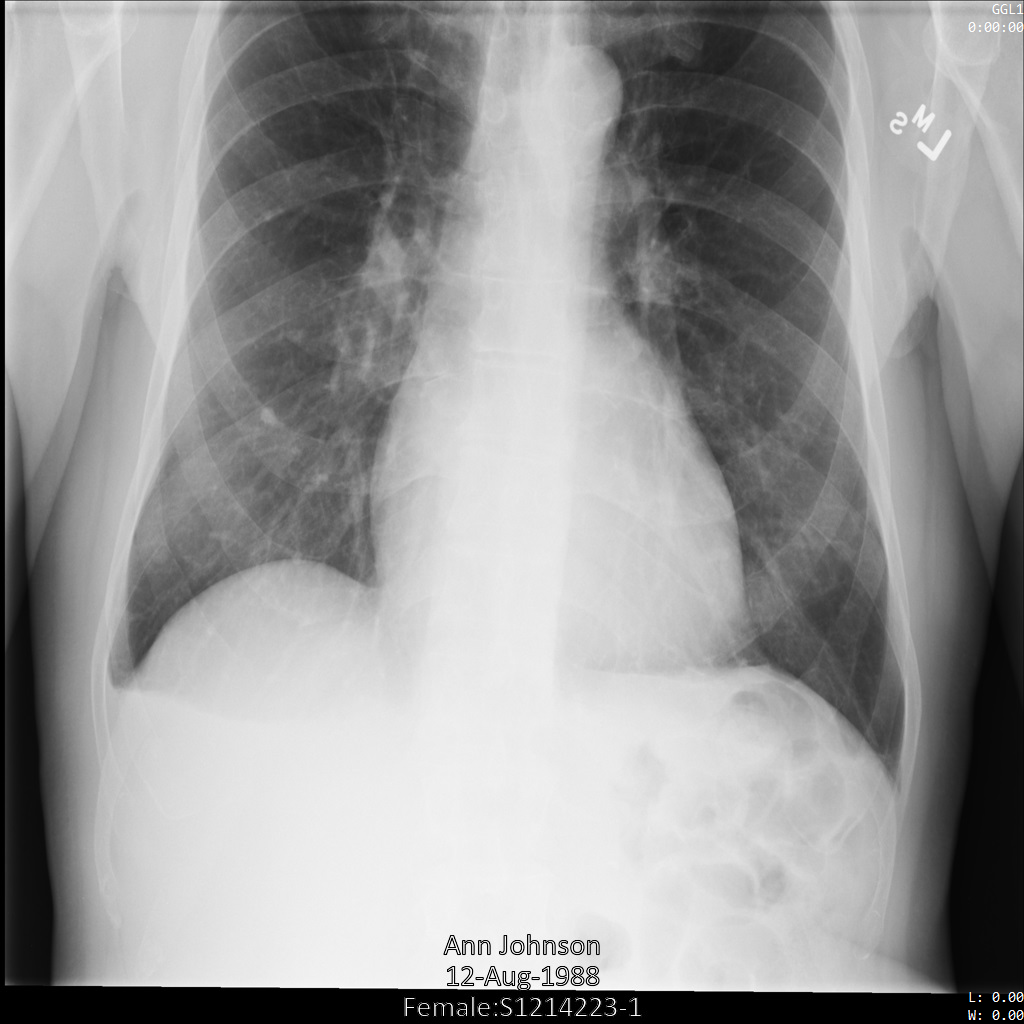

Contoh dalam panduan ini menggunakan satu instance DICOM, tetapi Anda juga dapat menghilangkan identitas beberapa instance.

Setiap bagian berikut memberikan contoh cara melakukan de-identifikasi data DICOM menggunakan berbagai metode. Output gambar yang tidak diidentifikasi disediakan dengan setiap sampel. Setiap sampel menggunakan gambar asli berikut sebagai input:

Anda dapat membandingkan gambar output dari setiap operasi penghapusan identitas dengan gambar asli ini untuk melihat efek operasi.

Gambar berikut menunjukkan hasil rontgen pasien yang tidak disamarkan:

Setelah mengirimkan gambar ke Cloud Healthcare API menggunakan opsi REDACT_SENSITIVE_TEXT, gambar akan muncul sebagai berikut:

Anda dapat melihat bahwa hal berikut terjadi:

PERSON_NAMEdi kiri bawah gambar disamarkanDATEdi kiri bawah gambar disamarkan

Jenis kelamin pasien tidak disamarkan karena tidak dianggap sebagai teks sensitif menurut infoType DICOM default.